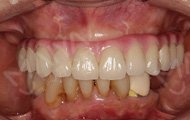

距离我上次做种牙手术,又一个多月了。今天来院复诊,“现在,我的牙好了,整个人精神面貌也恢复了,种回一口好牙,现在不仅恢复了身体健康,还找回了缺牙前那种想吃就吃的好心情,什么果什么肉随便吃,消化好吃嘛嘛香!”复查时,肖阿姨激动地说。虽然要来医院进行牙齿维护,但是为了我的牙齿健康,还是得坚持,毕竟牙齿陪伴一生,没有了它吃什么都没味道。真的非常感谢麦芽给了我再尝美味的机会。